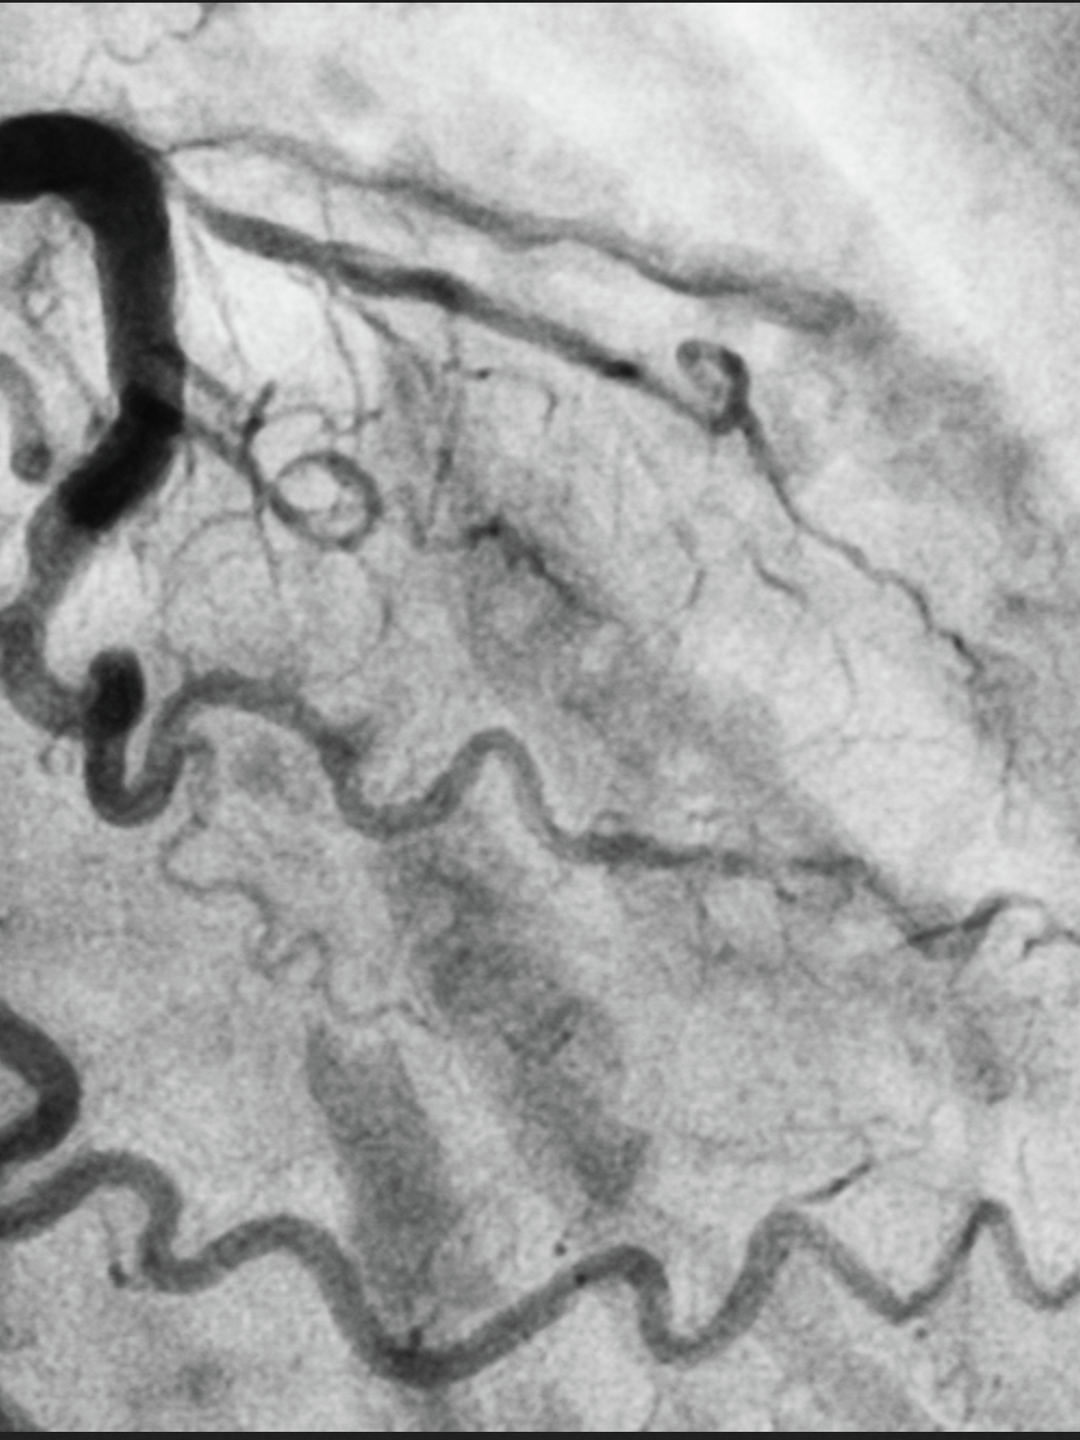

Robotic assisted minimally invasive direct coronary artery bypass grafting (RA-MIDCAB) for revascularization of the left anterior descending (LAD) coronary artery has joined the panoply of advanced cardiac procedures at Penn Cardiac Surgery.

RA-MIDCAB is performed via mini-thoracotomy, and has the advantage of avoiding both sternotomy and cardiopulmonary bypass. At Penn Cardiovascular Surgery, the procedure is offered to patients requiring single-vessel left internal mammary artery (LIMA)-to-LAD intervention as well as to patients at high risk for sternotomy and cardiopulmonary bypass. The LAD provides blood to the entire front wall of the heart muscle and is thus considered the principal target in coronary artery revascularization. The internal mammary arteries are preferred as pedicle grafts for their resistance to atherosclerosis.

Chase Brown, MD, is performing RA-MIDCAB at Penn Cardiovascular Surgery as a component of staged hybrid procedures involving CABG followed at a later date by percutaneous coronary intervention.